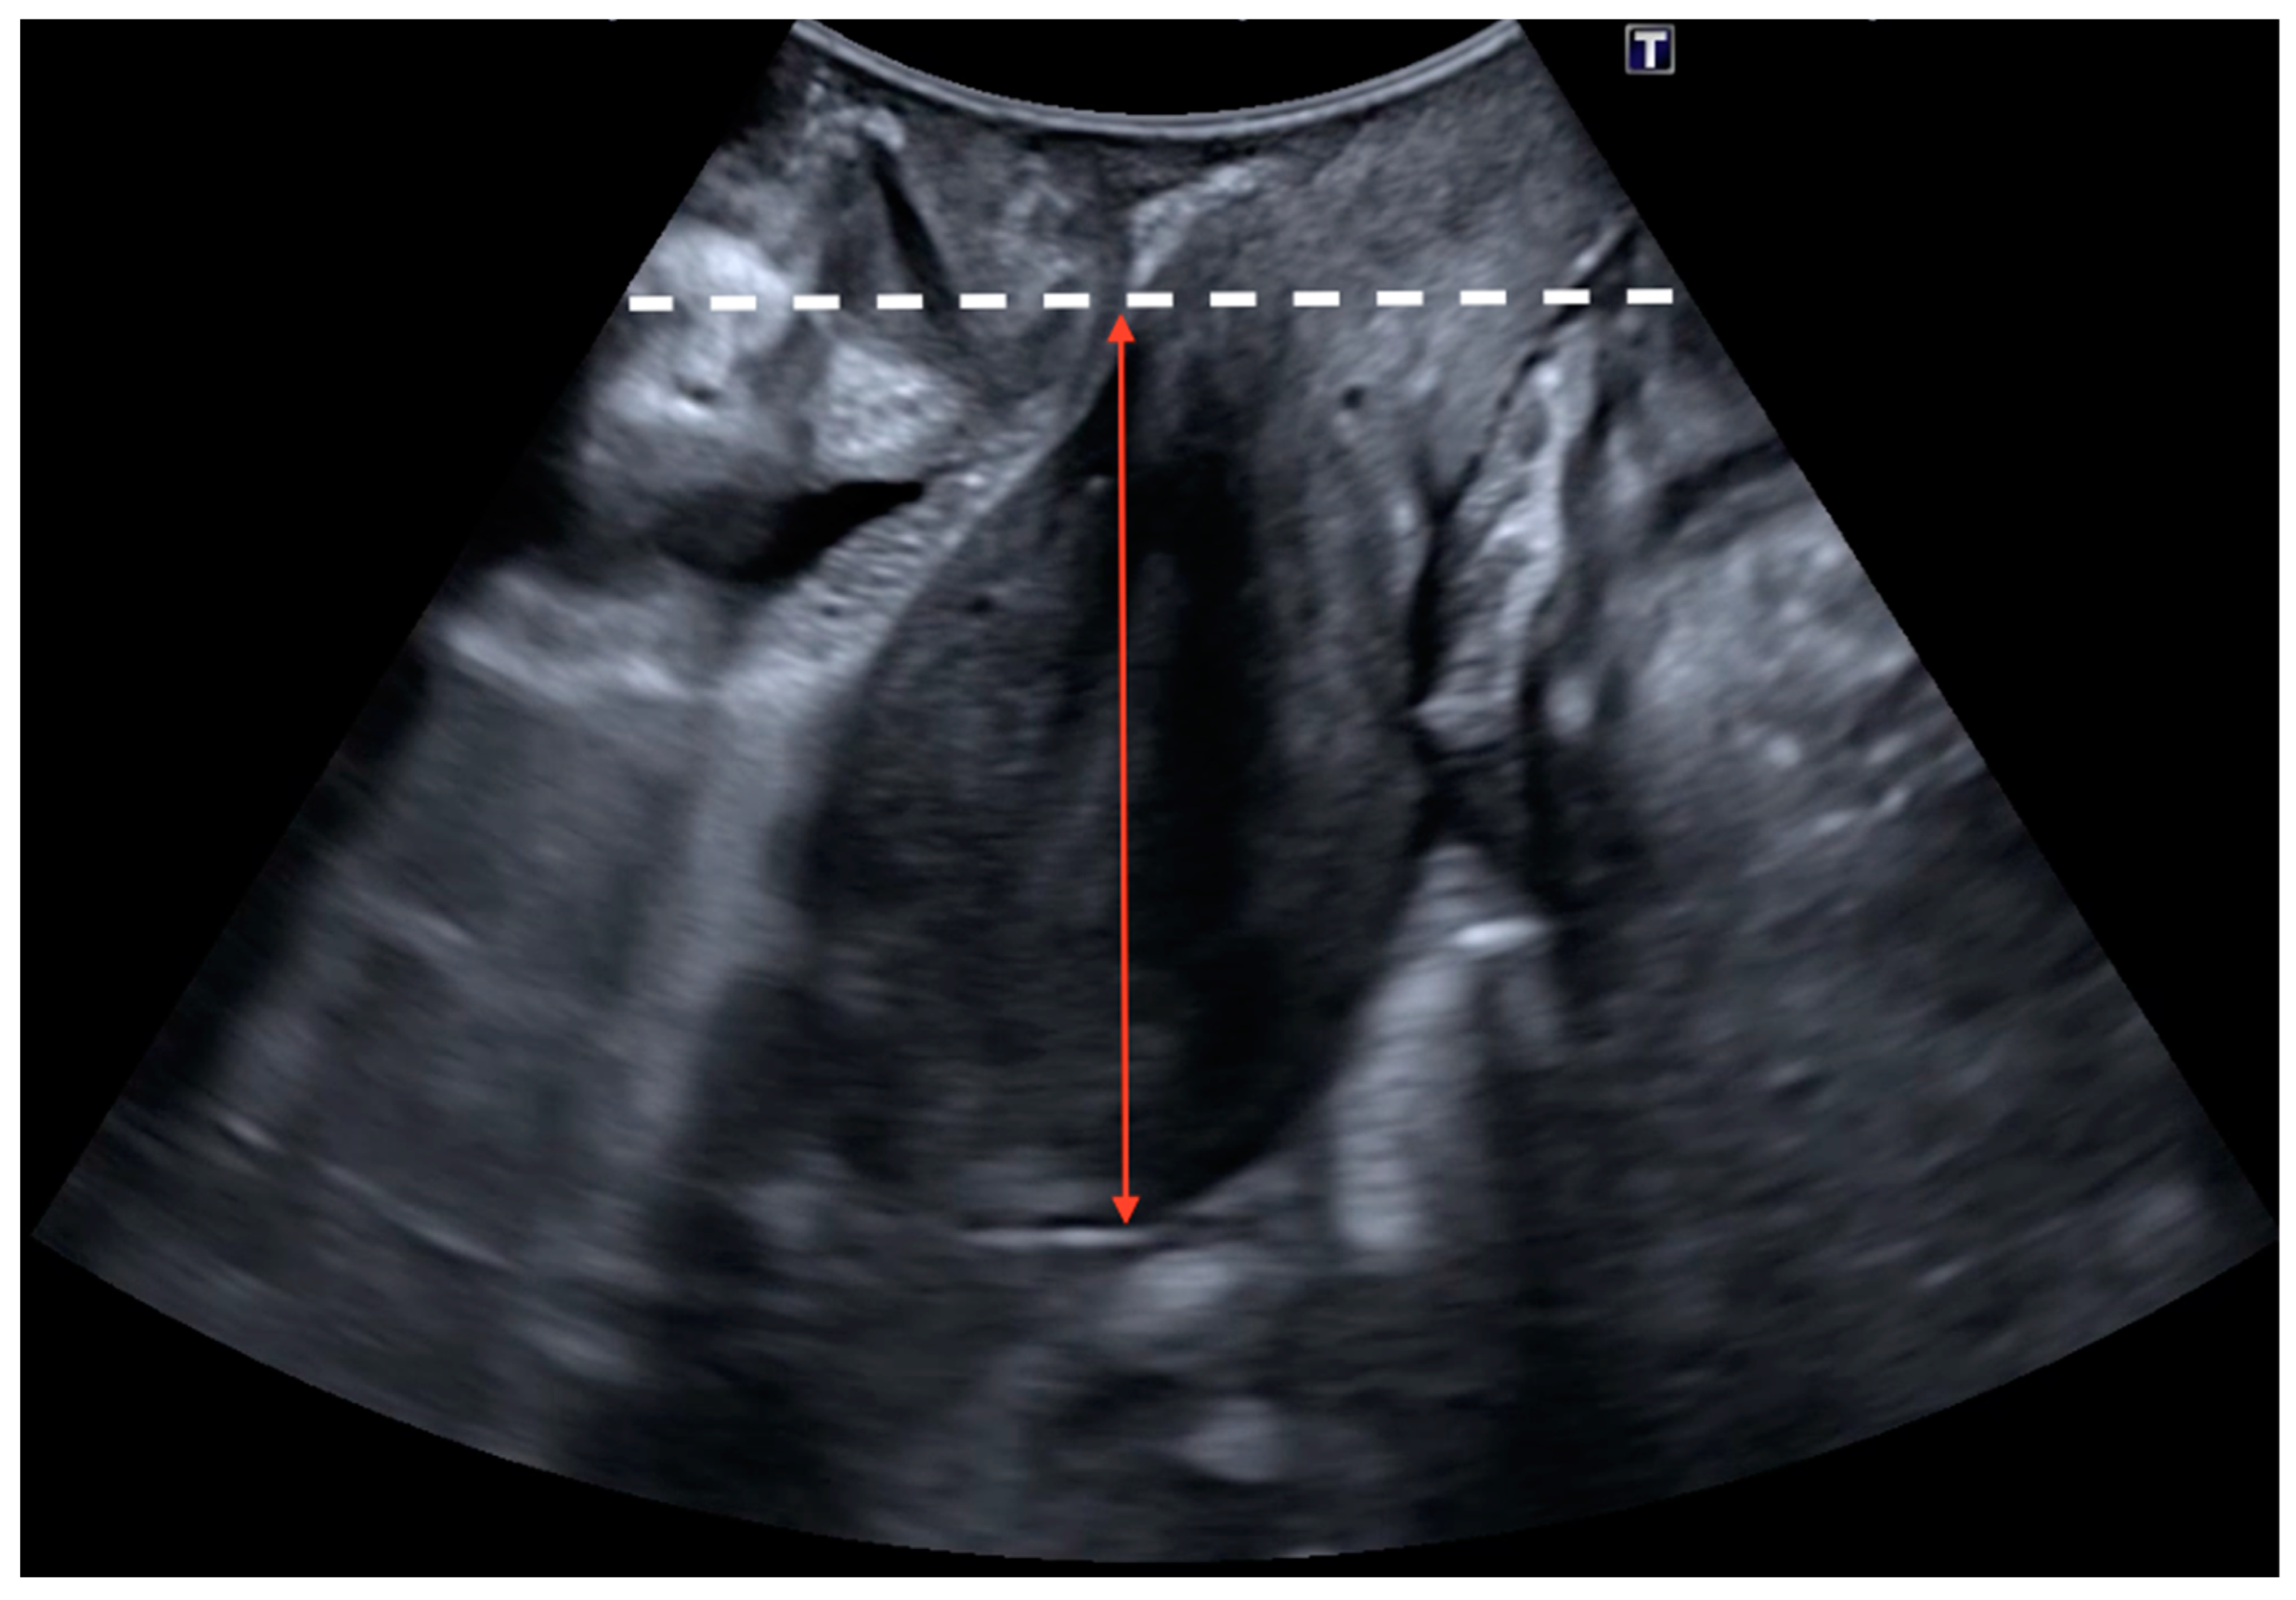

2.2. Ultrasound Examination